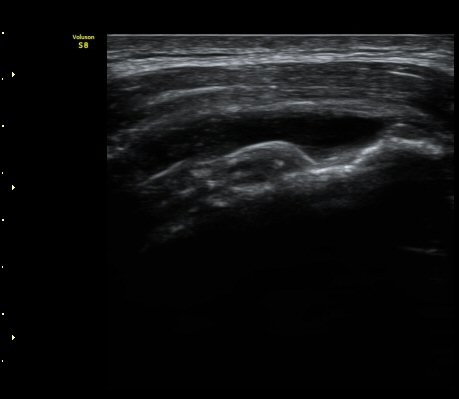

°ß°©ÇÏ±Ù°Ç Á¾´Ü¸é°Ë»ç¿¡¼­ ÀÌ»ó ¼Ò°ßÀ» º¸ÀÌÁö ¾Ê´Â´Ù(»çÁø 2)